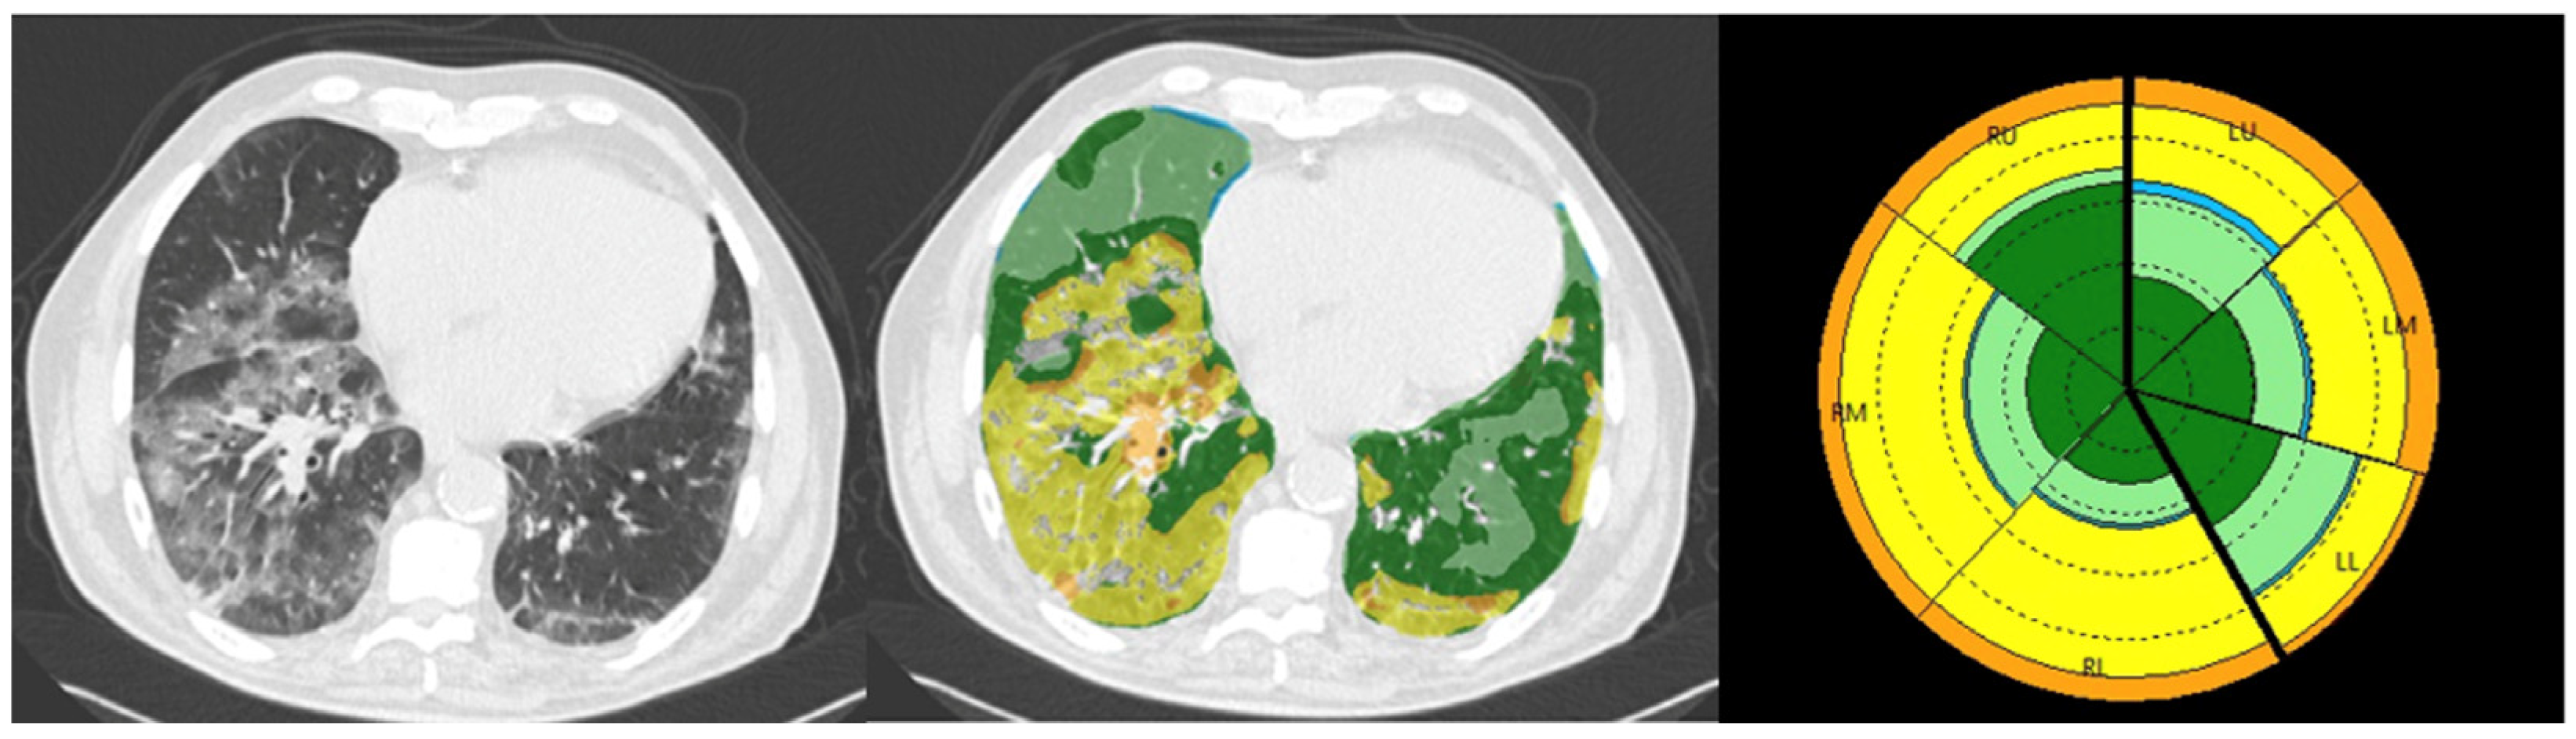

2.4. Density Mask Technique

2.5. Texture Analysis